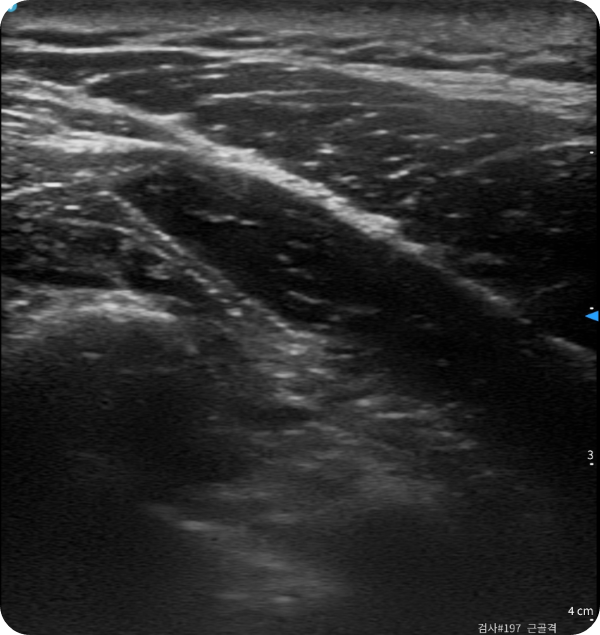

한의사의 손끝 감각인 촉진(Palpation)에 초음파 영상 기기의 활용으로,

치료의 정밀함을 더하였습니다.

가령, 해부학적 구조가 복잡한 목이나 어깨 관절을 치료할 때,

초음파를 통해 병변 부위를 실시간으로 확인하며 약침(藥鍼)을 시술합니다.

이를 통해 신경이나 혈관 손상을 방지하고,

치료 약물을 정확한 위치에 주입하여 치료 효율을 높입니다.